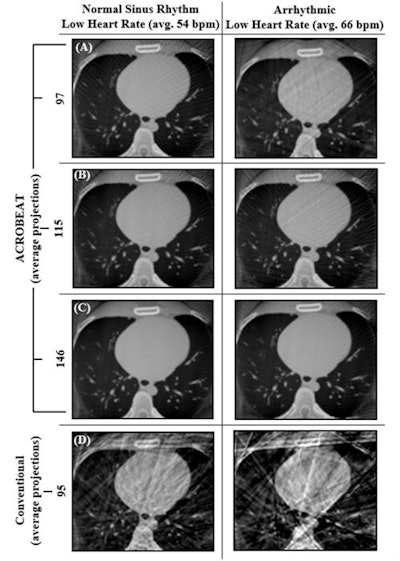

In simulations of the conventional protocol, the C-arm completes six rotations, acquiring a total of 990 projections in a scan time of 42 sec. Roughly 10% of these were used for image reconstruction. For ACROBEAT, the researchers performed three simulations for each scenario, acquiring around 100, 125, and 160 evenly spaced projections in scan times of between 25 sec and 71 sec. All projections were used in image reconstruction.

Cardiac images reconstructed using the conventional protocol contained streak and blurring artifacts for all three ECG traces. In all ACROBEAT simulations, these artifacts almost completely disappeared.

For all ECG traces and 10% acquisition windows, ACROBEAT increased the contrast-to-noise (C/N) ratio compared with the conventional protocol, indicating better visibility of image features. The edge response width (ERW), a measure of boundary sharpness between adjacent regions, was also lower (indicating sharper images) in ACROBEAT simulations than in equivalent conventional images.